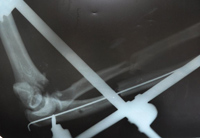

С  2009г  начали  выполнять  протезирование  тазобедренного  сустава  однополюсными  гемипротезами.  Широко  используется  накостный  остеосинтез,  интрамедулярный  остеосинтез  с  блокированием,  чрезкостный остеосинтез  (ЧКОС).

"после операции"